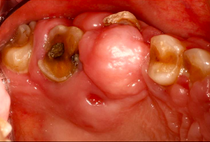

A 65-year-old female on antihypertensives and immunosuppressants presented with severe gum swelling, inability to chew, and difficulty maintaining oral hygiene. This led to multiple decayed and periodontally compromised teeth, worsening her overall condition.

Drug-influenced gingival overgrowth or ‘DIGO’ in short, manifests as abnormal swelling of the gingiva.

- The condition is usually caused by adverse reactions to certain drugs such as antihypertensives, anticonvulsants or immunosuppressants.

- As the gum tissues become significantly larger, it may impede normal masticatory function, daily oral hygiene, and aesthetics, severely diminishing one’s quality of life. (Sabarudin et al. 2022)

Before Treatment